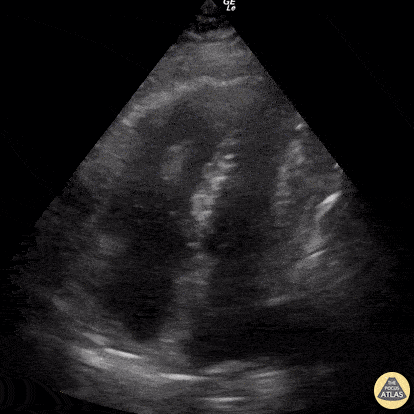

60 year-old smoker presents with dyspnea and chest pain. Apical 4 chamber view is notable for a thrombus within the RV and associated evidence of RV strain including increased RV size and impaired systolic function with sparing of the apex (known as McConnell’s sign). Renato Tambelli, @R_Tambelli Emergency Physician Hospital das Clínicas de Marília, Sao Paulo/Brazil